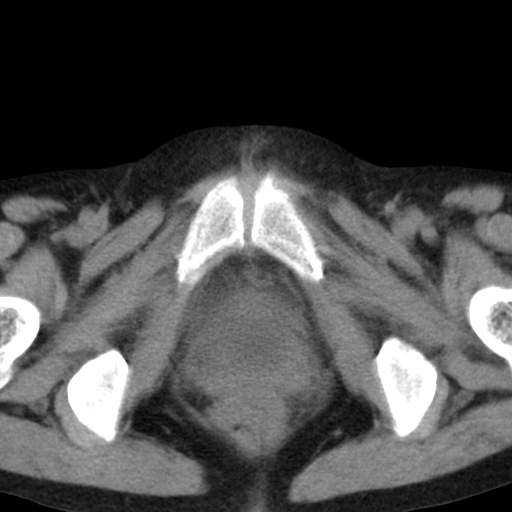

女,70,腹部间断性胀痛三月余

子宫宫腔及双侧附件积液,原因?

考虑卵巢囊腺瘤,不排除囊腺癌。

考虑卵巢囊腺瘤或囊腺癌。实质成分太多,考虑后者可能性大.

年龄较大还是恶性可能大,不排除库肯勃瘤

双侧卵巢粘液性囊腺癌,不多赘述。

考虑卵巢囊腺瘤;囊腺癌不能排除(理由:病人年龄较大,病灶外形欠规整、囊实相间,实性成分较多均支持囊腺癌)。要是能听听九目段老师的点评就好了!

年龄较大,囊实相间,实性成分较多均支持囊腺癌。

考虑囊腺癌,子宫病变不能排除吧,建议mri检查。